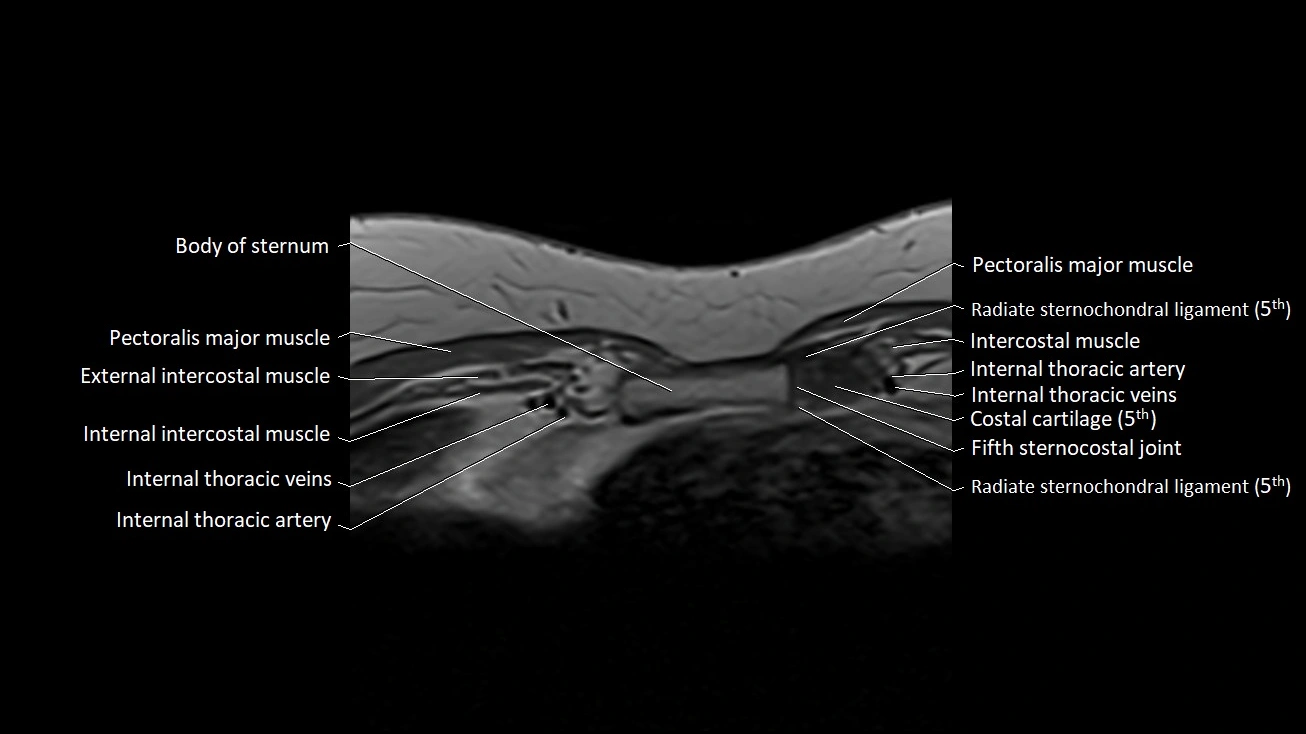

MRI images

image